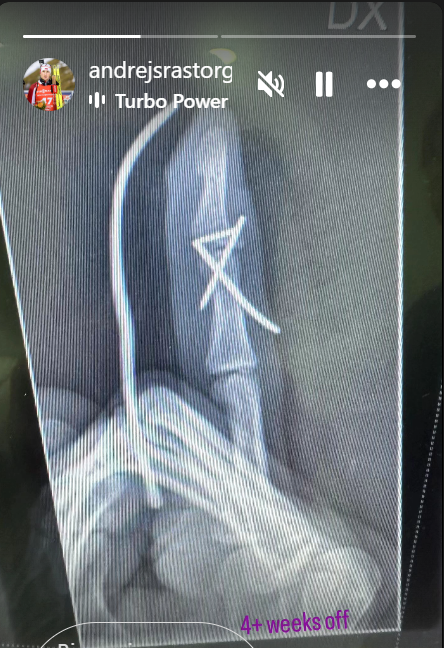

Андрейс достроково завершив виступи через перелом пальця, який він отримав унаслідок побиття тренером збірної Ілмарсом Бріцісом під час чемпіонату світу-2025.

"На жаль, останній старт сезону 2024/25 уже відбувся.

Палець зламаний, але не Андрейс. Дякую всім за підтримку!", – написав Расторгуєвс.